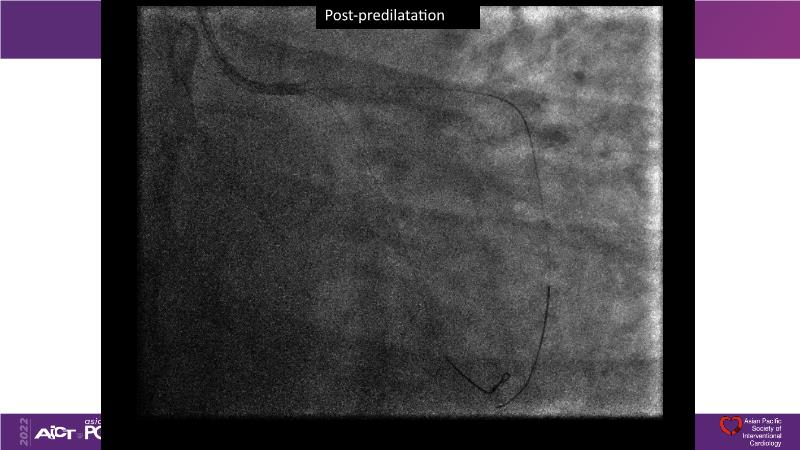

Consult this session to understand the technology and scientific evidence of the novel sirolimus drug-coated balloon, to learn its utility for PCI in a variety of lesion and patient subsets and to understand the evidence and outcomes in real-world patients.

- To learn the utility of the DCB for PCI in a variety of lesion and patient subsets